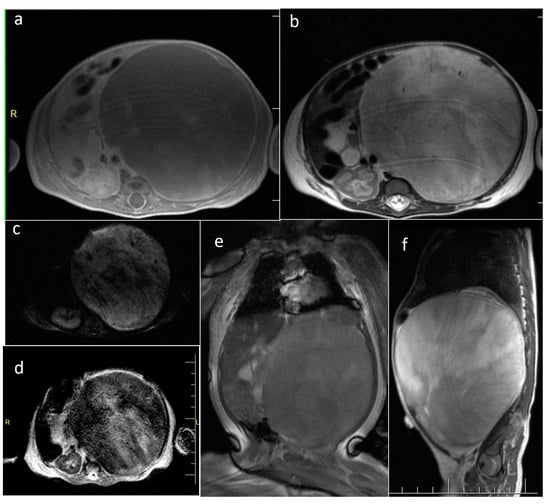

| Wilms tumor | kidney | 1 | 366.9 | yes (548) | Mixed | N/A | yes (solid part) |

| Hepatoblastoma | liver | 1 | 282 | yes (770) | mixed | No | yes (solid part) |

| Mesenchymal hamartoma | liver | 1 | 157 | N/A | Cystic | N/A | N/A |